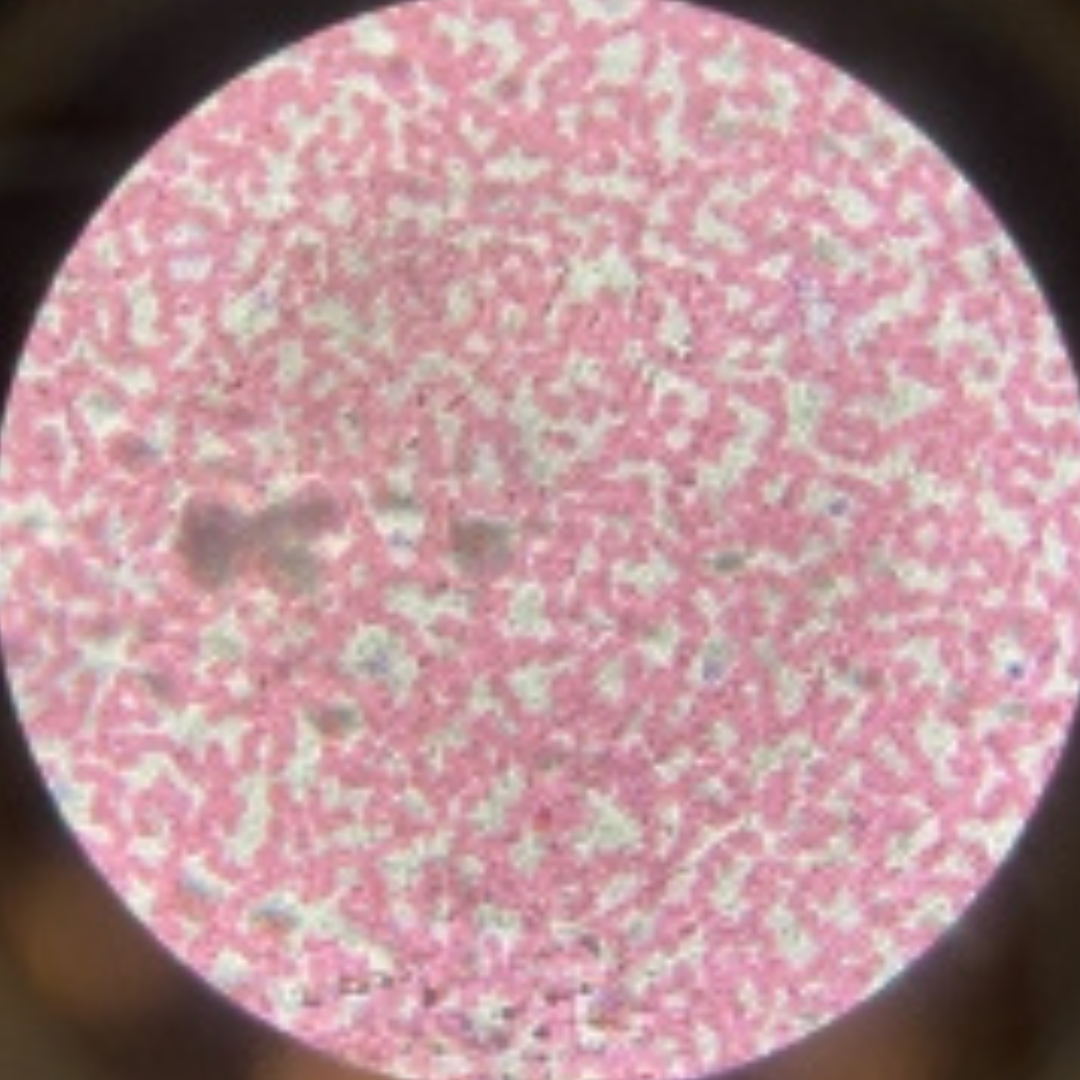

Blood

Blood